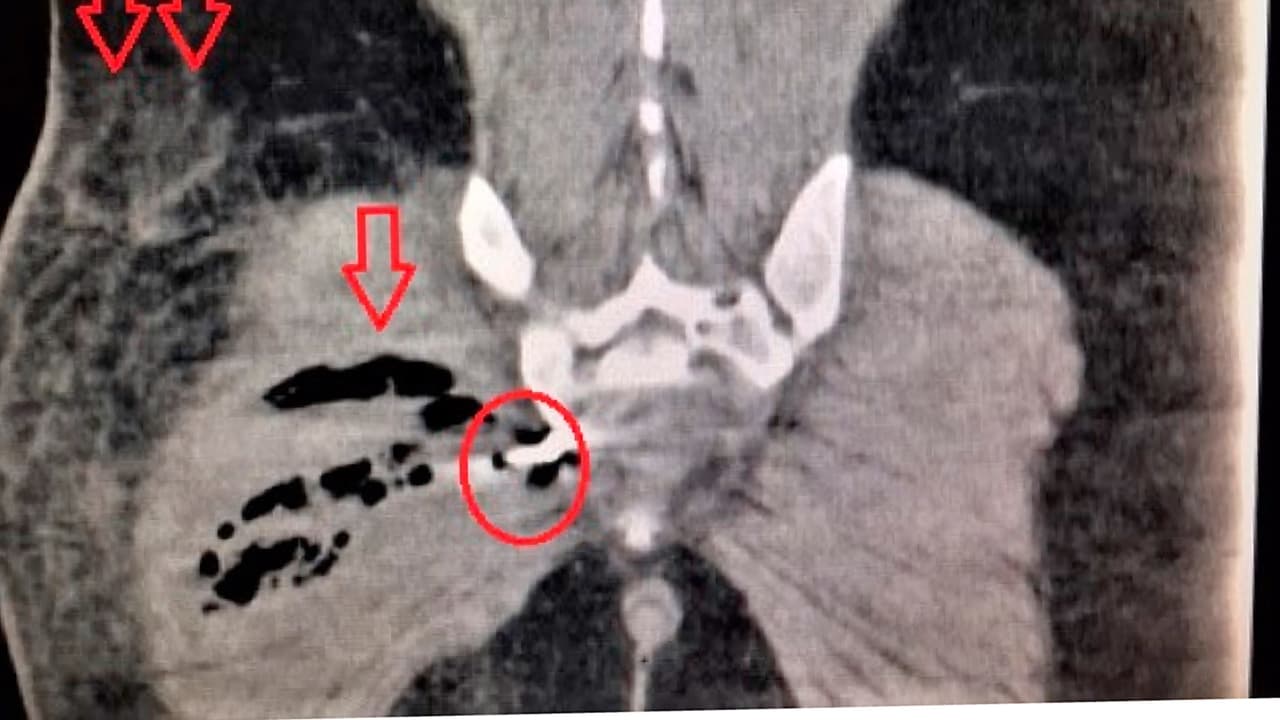

Una tomografía computarizada del abdomen del paciente, reveló una “perforación rectal y un objeto que parecía ser un destornillador”, según un informe del Centro Nacional de Biotecnología.

Los doctores del hospital Kendall Regional decidieron operarlo y encontraron que la parte metálica de la herramienta había perforado el recto del hombre. Durante la intervención quirúrgica drenaron un absceso en el glúteo derecho y le hicieron una colostomía.